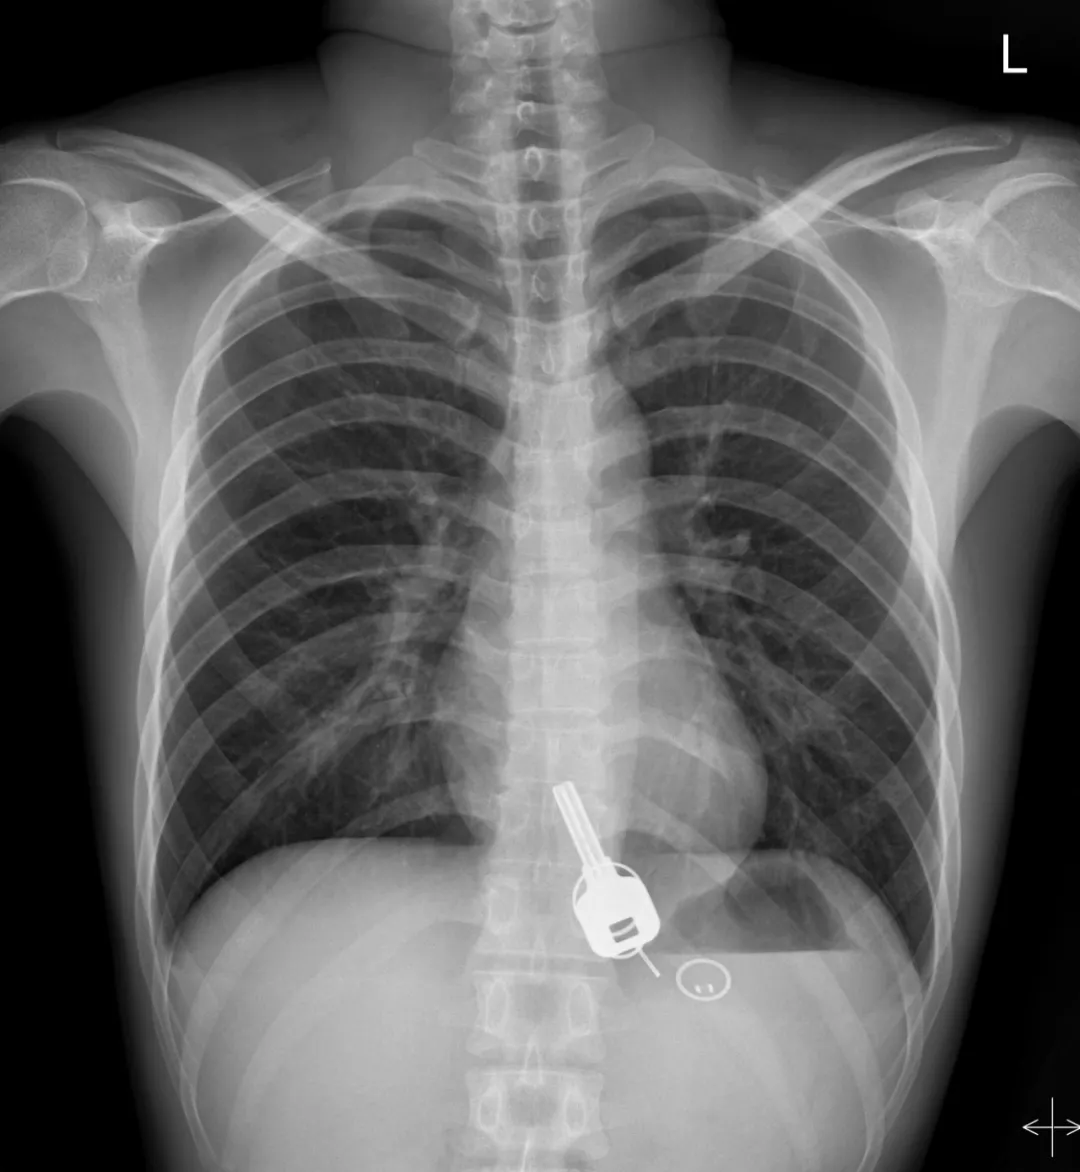

而下面東莞小哥喝酒喝到吞鑰匙

廣東東莞的常先生酒后回家找不到鑰匙,酒醒后他感到胸口疼痛,去醫(yī)院一查,發(fā)現(xiàn)一把鐵鑰匙、2個(gè)鑰匙扣、1個(gè)門禁牌清楚顯示在肚子胃區(qū)的位置上。

醫(yī)生準(zhǔn)備在胃鏡下取出鑰匙,不料,因鑰匙太大在常先生喉嚨附近食管入口處卡住了,取不出來(lái),最后,醫(yī)生決定給常先生做無(wú)痛胃鏡,麻醉后,常先生食管入口處肌肉松弛,鑰匙終于順利取出!。